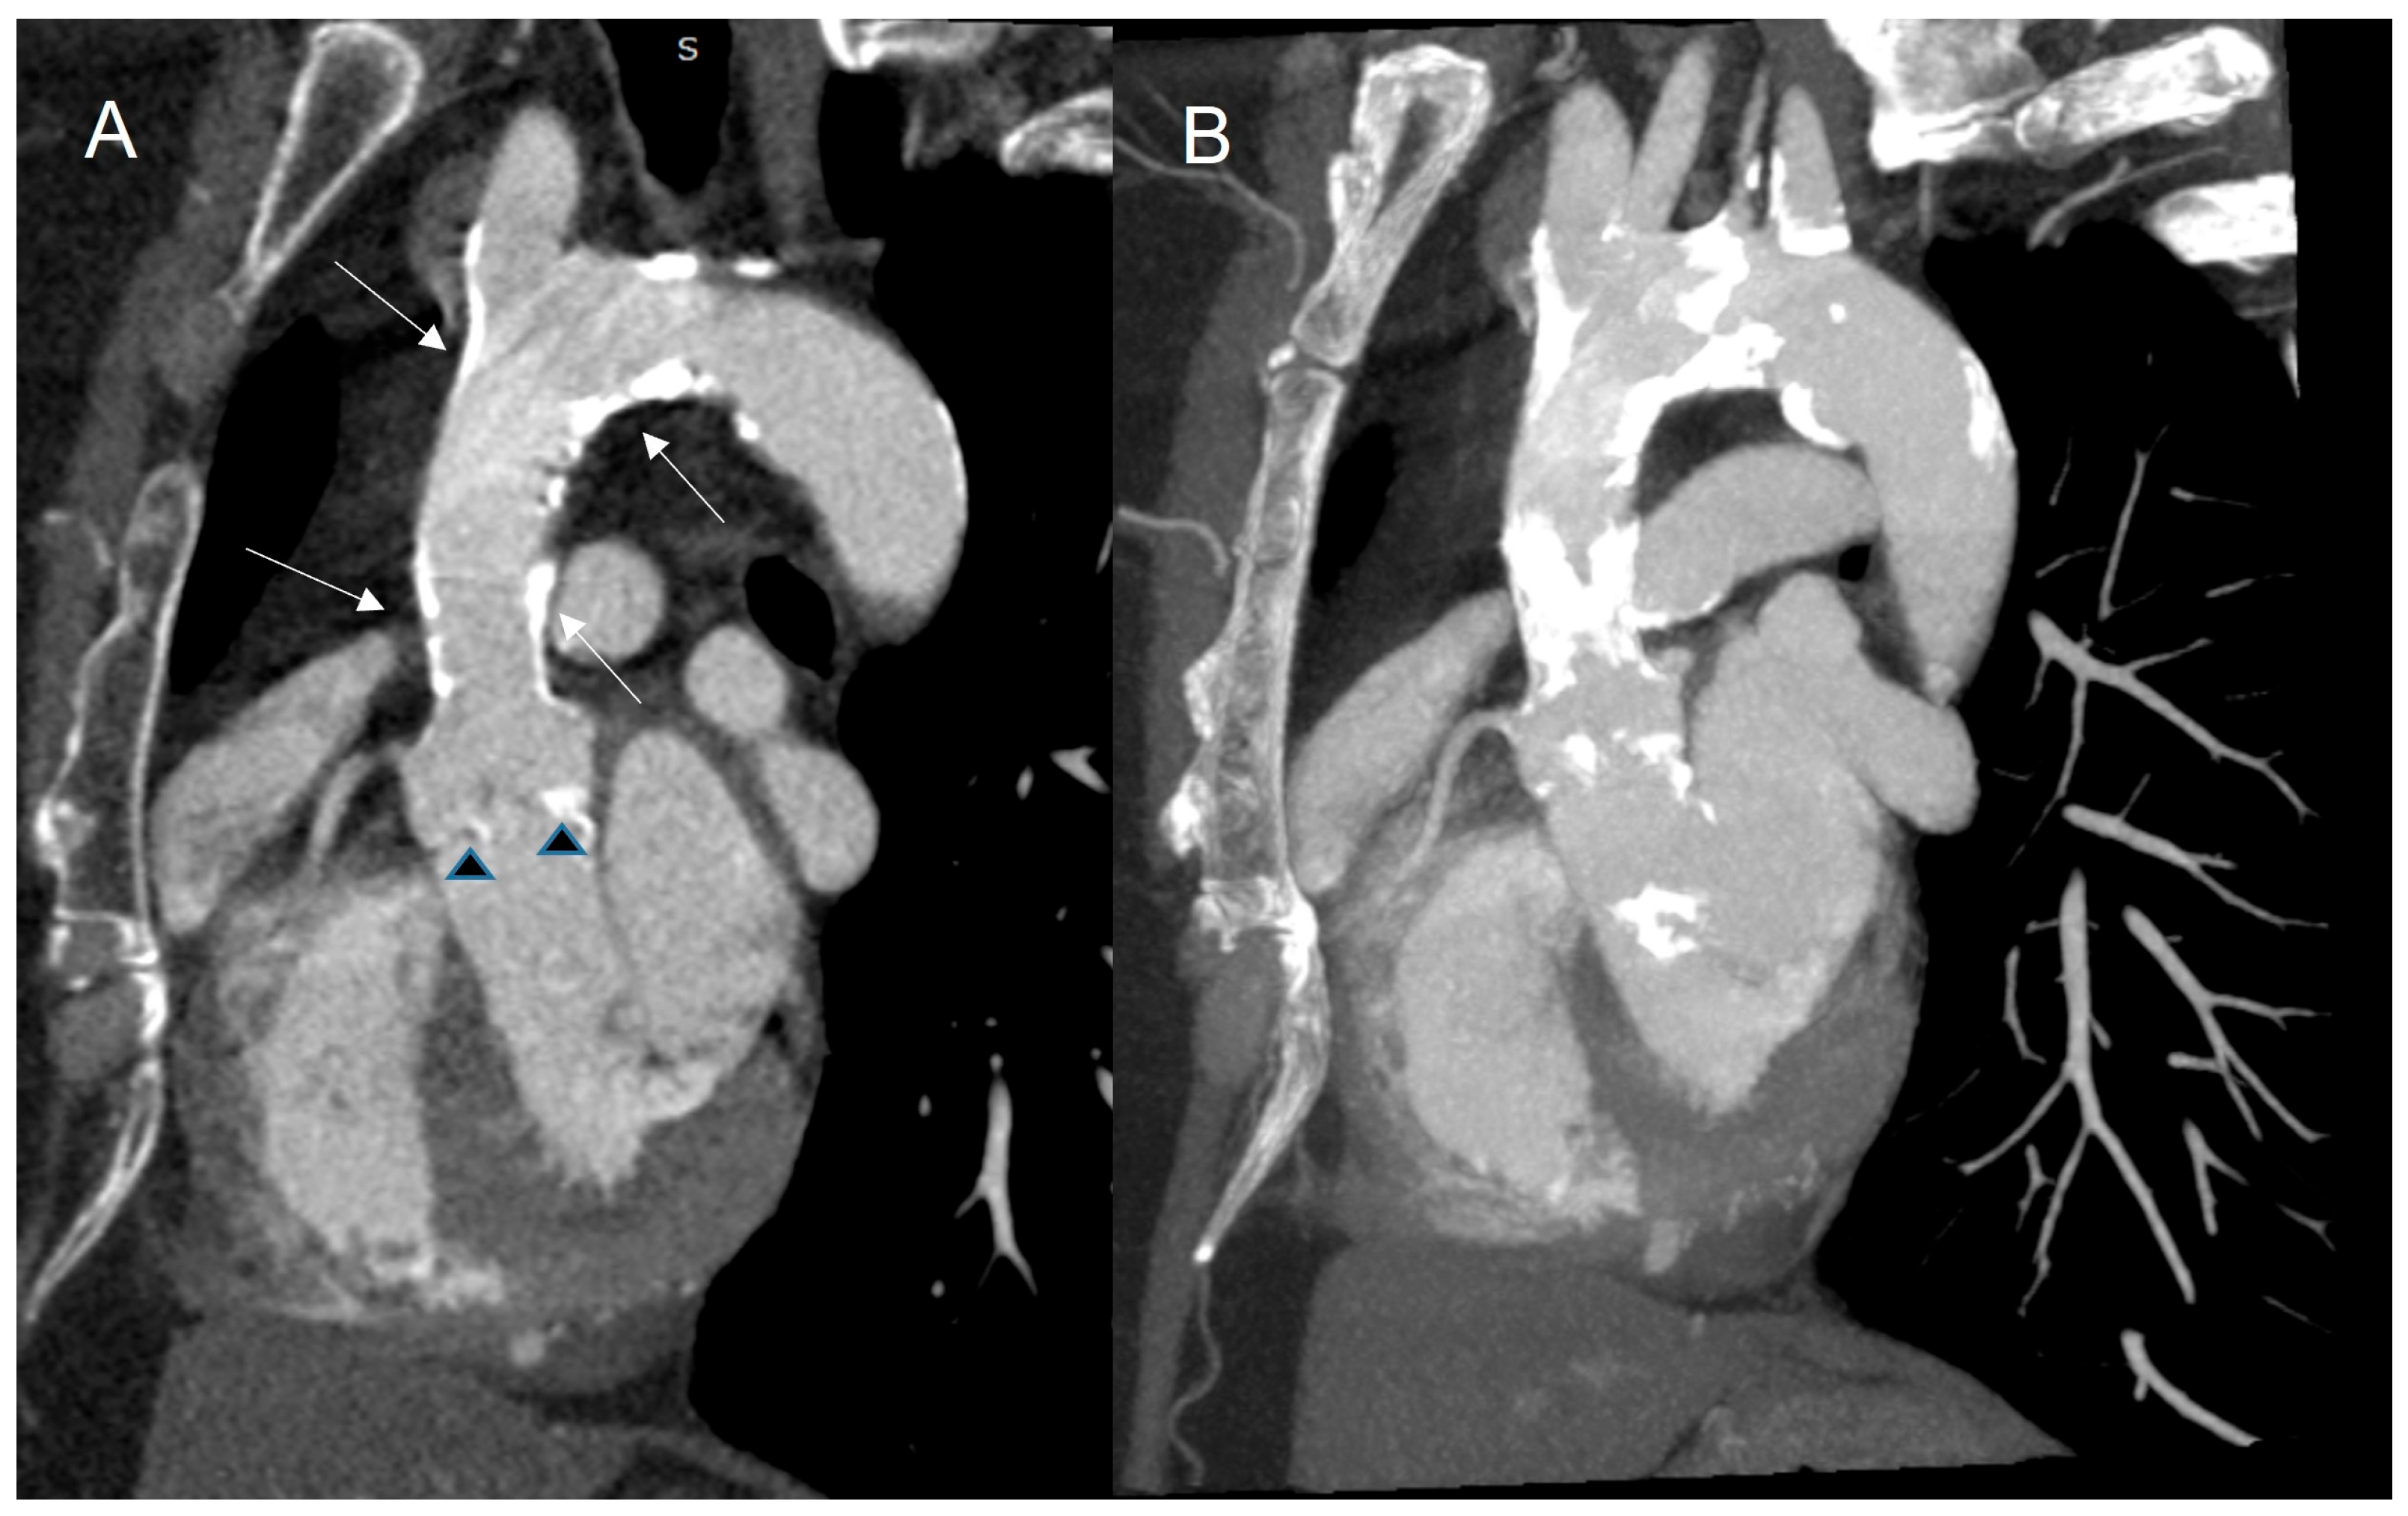

3.4. Cardiac Computed Tomography

3.4.1. Baseline Assessment

3.4.2. Identification of CTRCD

3.5. Role of CVMI in Assessing Late Cardiovascular Complications After Radiotherapy

3.5.1. Coronary Artery Disease

3.5.2. Valvular Heart Disease

3.5.3. Pericardial Disease